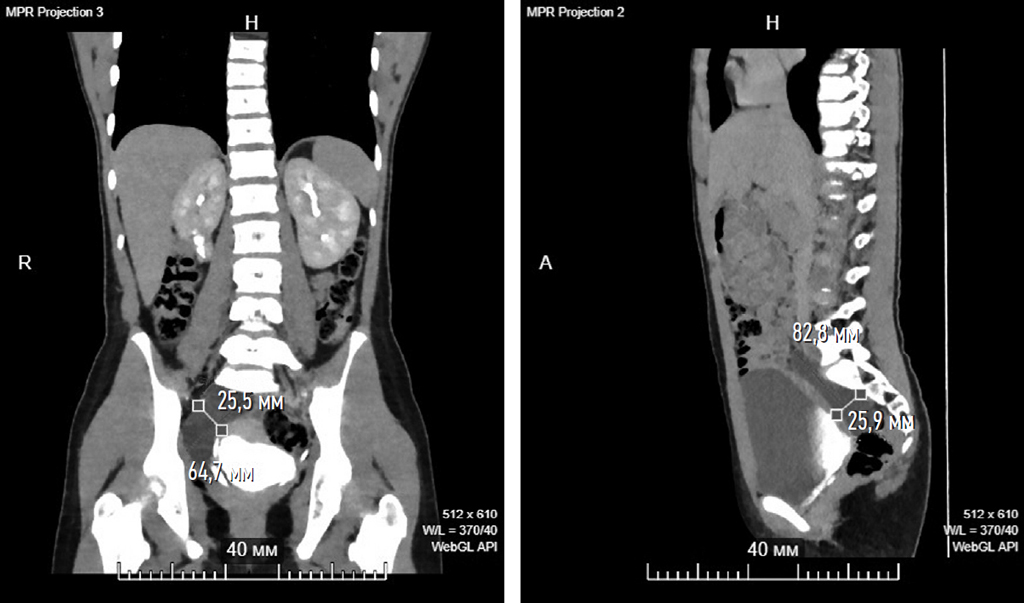

Fig. 1. Computed tomography urography (frontal and sagittal section), delayed phase. A cystic formation is visualized (dimensions are indicated), located along the lower third of the right ureter, which does not accumulate contrast

Рис. 1. Компьютерная томография-урография (фронтальный и сагиттальный срез), отсроченная фаза. Визуализируется кистозное образование (указаны размеры), располагающееся вдоль нижней трети правого мочеточника, ненакапливающее контраст

A 12-year-old female patient was examined in the gynecology department for a cystic lesion in the abdominal cavity (presumably a paraovarian cyst), which was found incidentally by ultrasound. Interestingly, the patient did not have any clinical symptoms or active urinary tract infections. Diagnostic laparoscopy revealed no ovarian cysts. A mass protruding into the peritoneal cavity was visualized in the retroperitoneal space. The patient underwent further evaluation. Computed tomography urography revealed a poorly defined retroperitoneal fluid collection without contrast enhancement, located near the right ureter (Fig. 1). The right kidney, however, showed no abnormalities. Cystography showed that the contours of the bladder were smooth and clear, and no diverticula, contrast leakage, or vesicoureteral reflux were found.